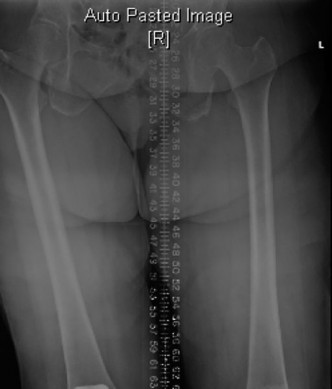

The correct answer is (D). Since the patient has an abnormality of alignment, it is important to obtain a 3-foot standing view to measure mechanical and anatomic axis (Fig. 7–10). MRI is not helpful in the setting of most revision TKR. Bone scan is not indicated as the implants are clearly loose on plain films. Metal allergy testing is not likely to be the cause of the implant failure given that radiographs are consistent with aseptic loosening.

Figure 7–10